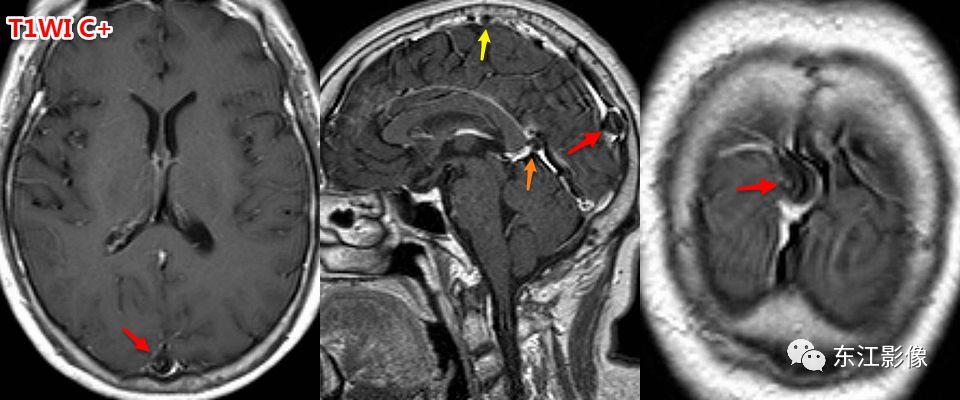

5. 脑脊液流动伪影

- 脑脊液流动伪影主要见于T2WI、FLAIR,主要是长TE序列容易出现流空效应的缘故。

- 但由于脑脊液流动方向、速率不一等因素的影响,呈现为非脑脊液信号影像,部分呈囊样。

- 常见于第三脑室、侧脑室室间孔旁区、脑干周围脑池(这些区域结构复杂)。

- 鉴别要点,T1WI、增强未能辨认;DWI与邻近一致的无信号;无占位效应。

桥前池脑脊液流动伪影。